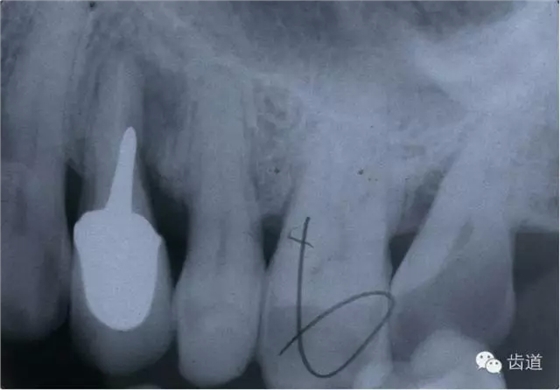

2.檢查:探診疼痛,且有鮮血;用根管長(zhǎng)度測(cè)量?jī)x探測(cè)可疑穿孔處,儀器發(fā)出報(bào)警聲;插診斷絲到可疑穿孔處拍X線片,可見(jiàn)診斷絲已超出髓腔范圍。